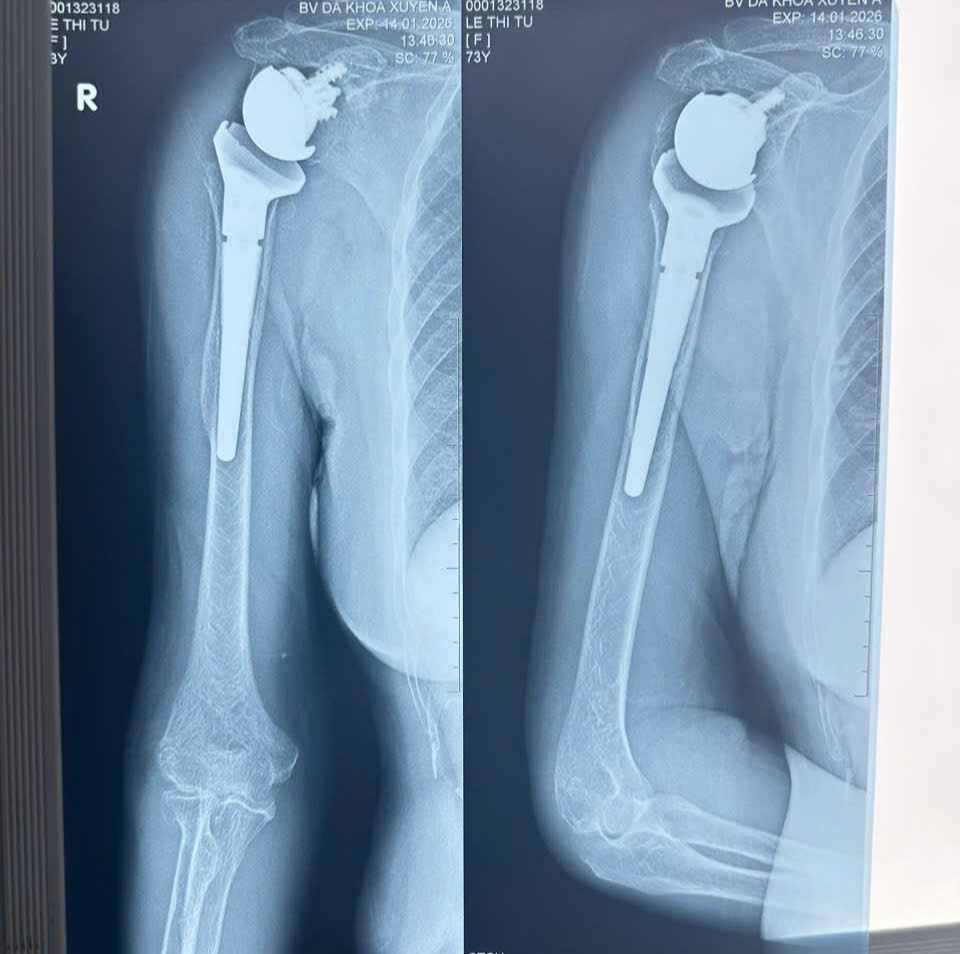

Kết quả chụp X-quang cho thấy bệnh nhân bị gãy nát đầu trên xương cánh tay bên phải thành nhiều mảnh nhỏ, các mảnh xương gãy rời rạc, chỏm xương cánh tay bị trật hoàn toàn khỏi ổ chảo xương bả vai, gây tổn thương nghiêm trọng cấu trúc khớp vai. Với tình trạng tổn thương phức tạp này, nếu không được phẫu thuật bệnh nhân sẽ đau đớn kéo dài, lâu dần có thể dẫn đến hoại tử chỏm xương và ổ chảo cánh tay, hạn chế khả năng vận động tay.

Hình ảnh X quang trước vào sau khi thực hiện phẫu thuật thay khớp vai đảo nghịch

Sau gần 2 giờ thực hiện, ca phẫu thuật thành công tốt đẹp, khớp vai nhân tạo được đặt đúng vị trí giải phẫu, cố định vững chắc. Ngay sau phẫu thuật, người bệnh cũng giảm đau rõ rệt. Dự kiến trong 2 tuần tiếp theo, người bệnh cần mang đai cố định khớp vai để đảm bảo quá trình lành thương, sau đó sẽ được hướng dẫn tập vật lý trị liệu – phục hồi chức năng theo phác đồ chuyên biệt, mục tiêu là giúp khớp vai lấy lại biên độ vận động, sức mạnh cơ và khả năng sinh hoạt gần như bình thường.